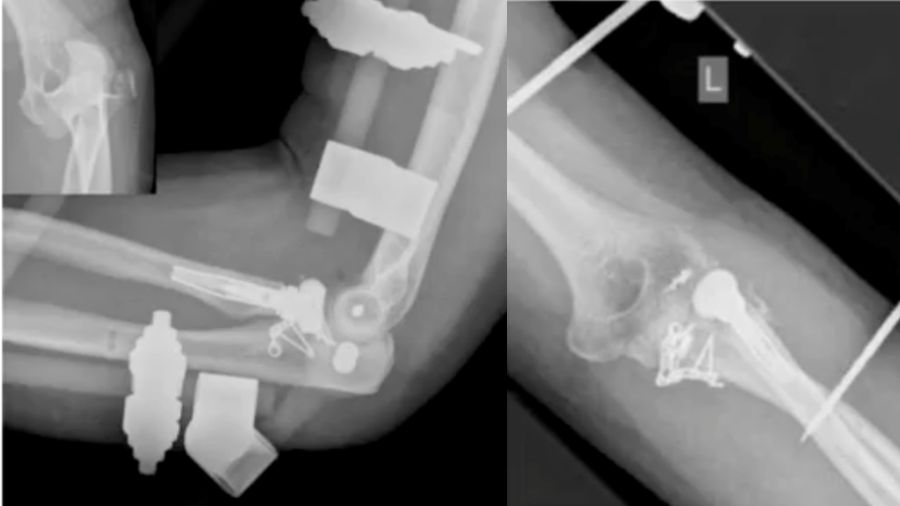

Case 2: 48-year-old male, fall from scaffold

A 48-year-old man presented with a luxated elbow, radial head fracture, and coronoid fracture. Despite initial surgery, a second CT scan revealed improper positioning of the radius head and a lateral shift in the elbow. Revised surgery was performed by fixing the coronoid plate and reattaching the lateral ligaments.